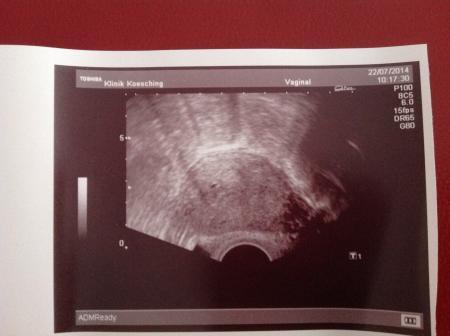

Ich bin wieder daheim und gut das wir abgewartet haben, denn heute konnten wir was in US erkennen. Ich wurde zwar nochmal über eine Pseudozyste, bzw. Pseudoschwangerschaft aufgeklärt, die auch durchaus bei 50% bei ELSS auftreten kann. Ich bin heute ssw 5+1, 22 Tage nach Transfer! Danke für euren vielen Beiträge!

Bild zu